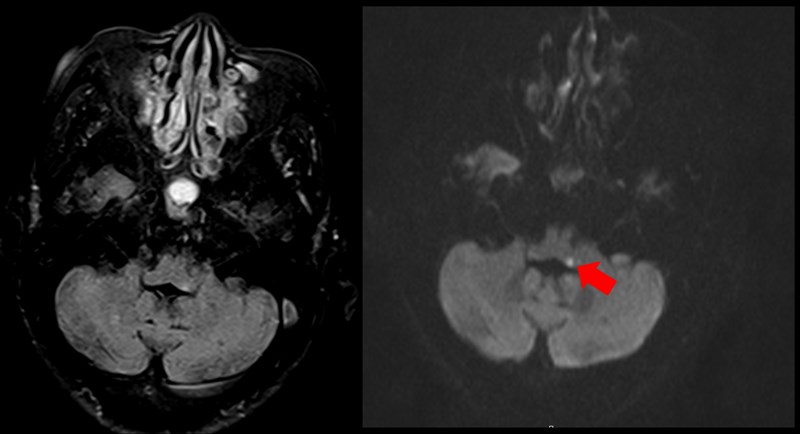

透過腦部核磁共振檢查,箭頭處亮點為血管梗塞位置;醫師診斷八旬婦為腦幹梗塞型中風。圖/恩主公醫院

恩主公醫院神經內科醫師朱海瑞,日前收治一名80歲婦人,本身有糖尿病與高血壓,某天起床時感到頭暈目眩,甚至想吐,家人以為是剛起床還沒吃飯、血糖過低;但是吃完早餐後,仍覺得頭暈不適,被家人送至急診就醫,因考量到婦人80歲高齡、且有心血管病史,因此會診神經內科,透過腦部核磁共振檢查,診斷婦人為腦幹梗塞型中風。